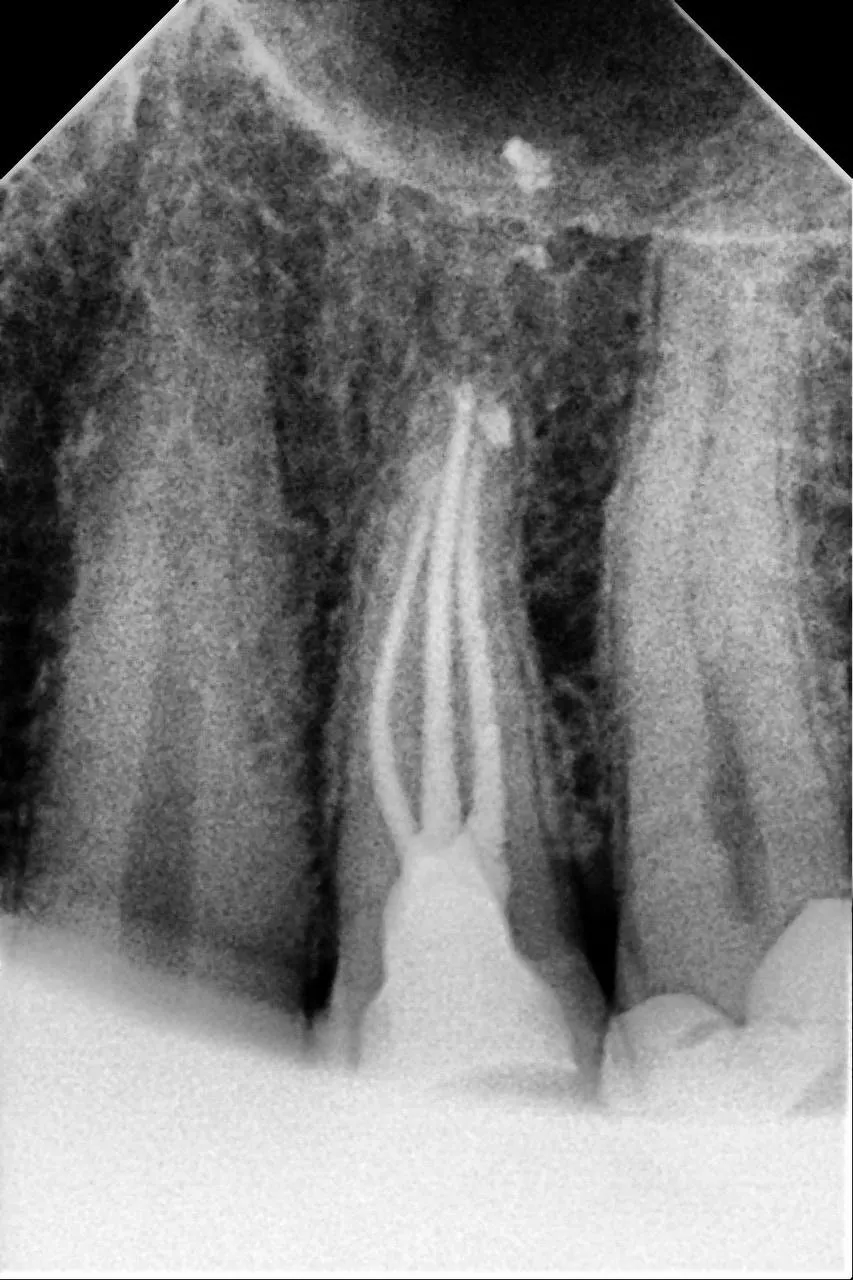

Вторинне ендо 14 зуба. Пропущений дистальний щічний канал